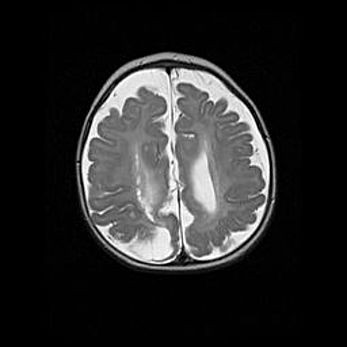

Открытая гидроцефалия.

Возраст: 9 месяцев 12 дней

Вес: 6800 г

Пол: мужской

Окружность головы: 41,5 см

Срок гестации: 28 недель

Гидроцефалия головного мозга у новорожденных имеет характерный признак: опережающий рост окружности головы приводит к визуально хорошо определяемой гидроцефальной форме сильно увеличенного в объёме черепа. Детские неврологи определяют следующие симптомы гидроцефалии у грудничков: выбухающий напряжённый родничок, частое запрокидывание головы, смещение глазных яблок к низу.